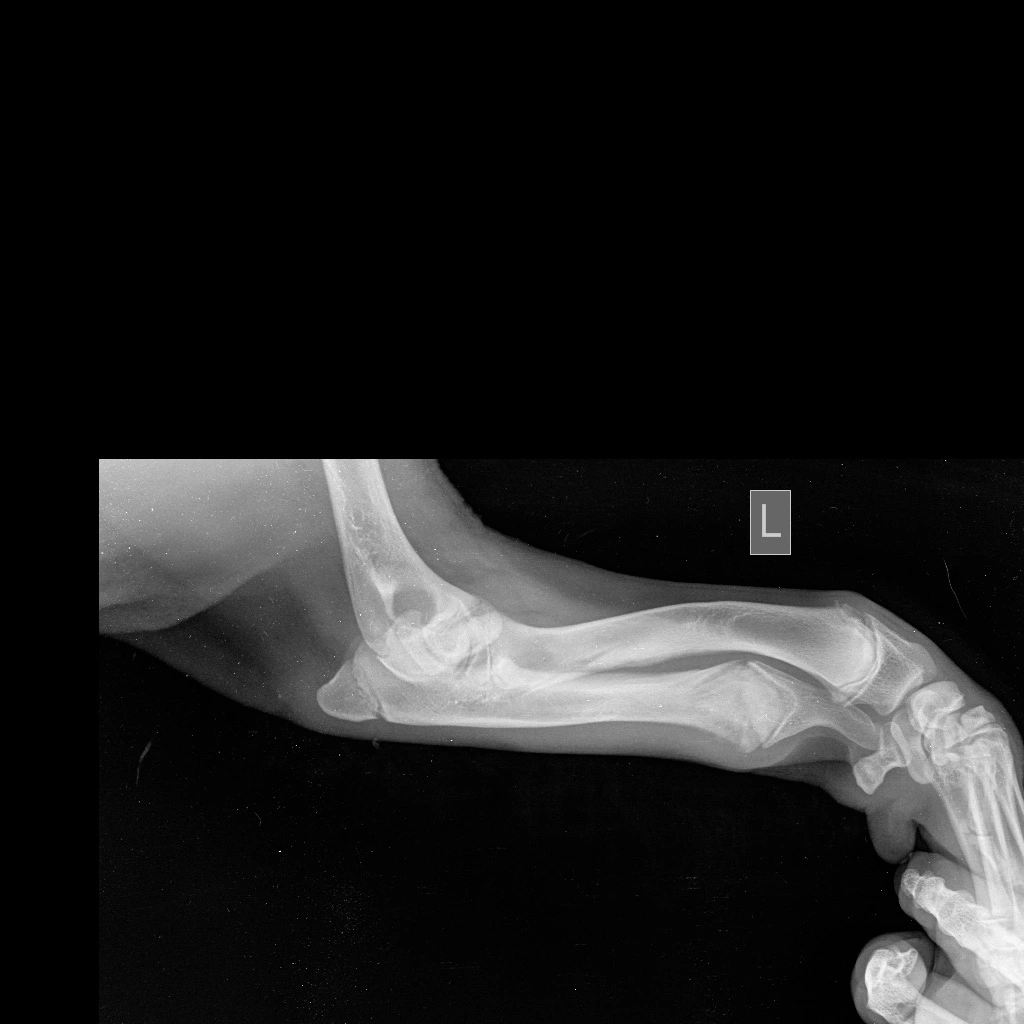

Предплечье состоит из двух костей (лучевой и локтевой), в норме они развиваются синхронно. При заболевании отмечается раннее закрытие зоны роста локтевой кости, что останавливает ее рост, в то время как лучевая кость продолжает увеличиваться в длину. Дальнейшему росту кости препятствуют локтевые и запястные суставы, что вызывает избыточное давление на них и искривление самой кости. Патологическое давление на сустав вызывает развитие дегенеративного изменения хряща (артроза, артрита, остеоартрита).

Основными клиническим признаками является нарастающая хромота и искривление лап в области запястья (так называемый «размет лап», а также припухлость в области локтевого сустава и его малоподвижность).

Диагноз ставится на основании анамнеза, ортопедического осмотра и инструментальных методов диагностики, таких как рентгенография и компьютерная томография (КТ), при которых врач может оценить стадию заболевания и выбрать подходящую тактику лечения.